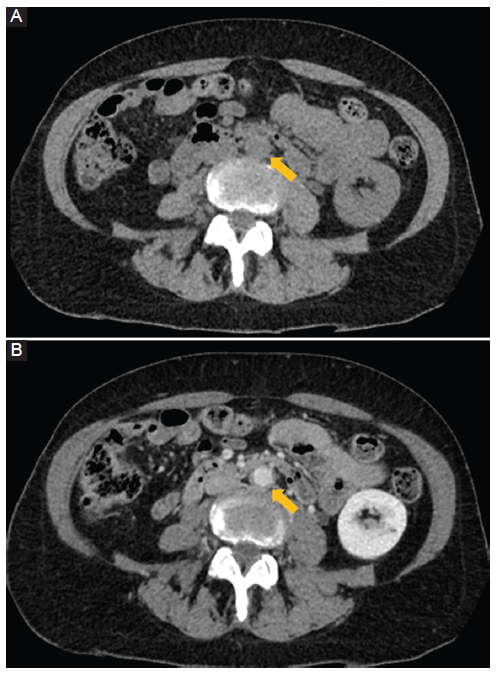

Figura 12

Fístula aorto-entérica. Mujer de 58 años. Dolor abdominal y sangrado gastrointestinal. TC con contraste cortes axiales A y B: el estudio muestra un aneurisma aórtico abdominal con comunicación y paso de medio de contraste (flecha) hacia el duodeno (flecha hueca). También hay presencia de gas en un trombo mural (punta de flecha) y cambios inflamatorios en los tejidos adyacentes (asterisco).